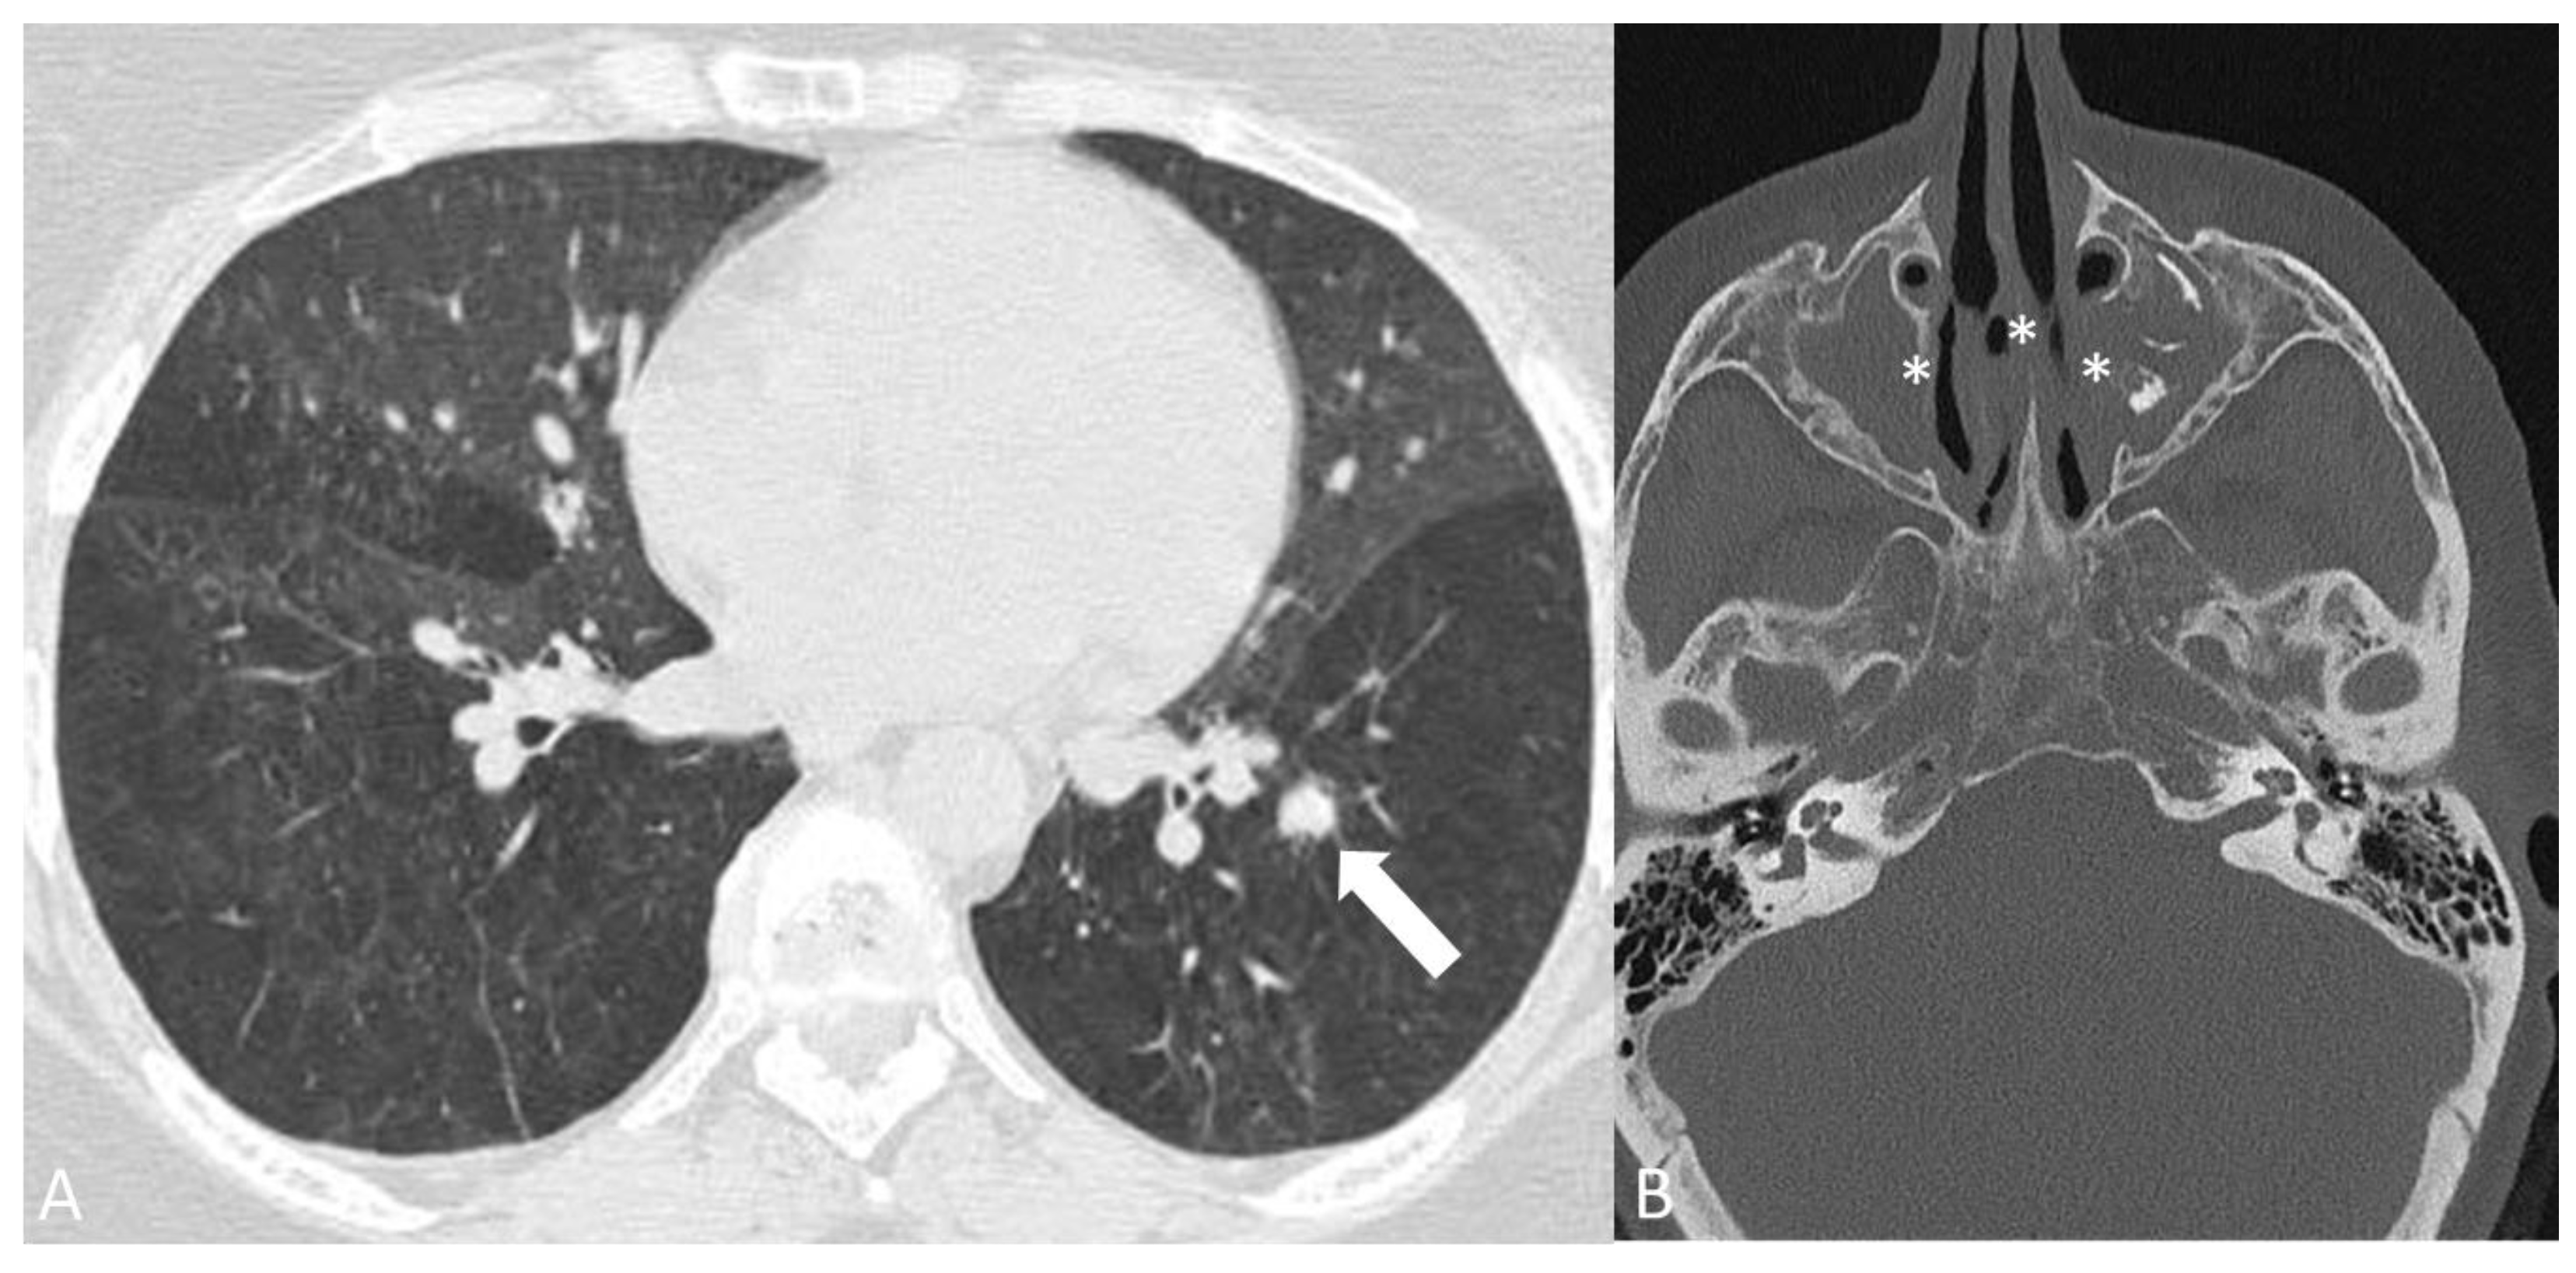

2.3.1. Granulomatosis with Polyangiitis

- Tee, Q.X.; Wong, A.; Nambiar, M.; Lau, K.K. Granulomatosis with polyangiitis: Common and uncommon presentations. J. Med. Imaging Radiat. Oncol. 2022, 66, 1089–1096. [Google Scholar] [CrossRef] [PubMed]

- Guneyli, S.; Ceylan, N.; Bayraktaroglu, S.; Gucenmez, S.; Aksu, K.; Kocacelebi, K.; Acar, T.; Savas, R.; Alper, H. Imaging findings of pulmonary granulomatosis with polyangiitis (Wegener’s granulomatosis): Lesions invading the pulmonary fissure, pleura or diaphragm mimicking malignancy. Wien. Klin. Wochenschr. 2016, 128, 809–815. [Google Scholar] [CrossRef] [PubMed]

- Castaner, E.; Alguersuari, A.; Andreu, M.; Gallardo, X.; Spinu, C.; Mata, J.M. Imaging findings in pulmonary vasculitis. In Seminars in Ultrasound, CT and MRI; WB Saunders: Philadelphia, PA, USA, 2012; Volume 33, pp. 567–579. [Google Scholar] [CrossRef]

- Mohammad, A.J.; Mortensen, K.H.; Babar, J.; Smith, R.; Jones, R.B.; Nakagomi, D.; Sivasothy, P.; Jayne, D.R.W. Pulmonary Involvement in Antineutrophil Cytoplasmic Antibodies (ANCA)-associated Vasculitis: The Influence of ANCA Subtype. J. Rheumatol. 2017, 44, 1458–1467. [Google Scholar] [CrossRef]